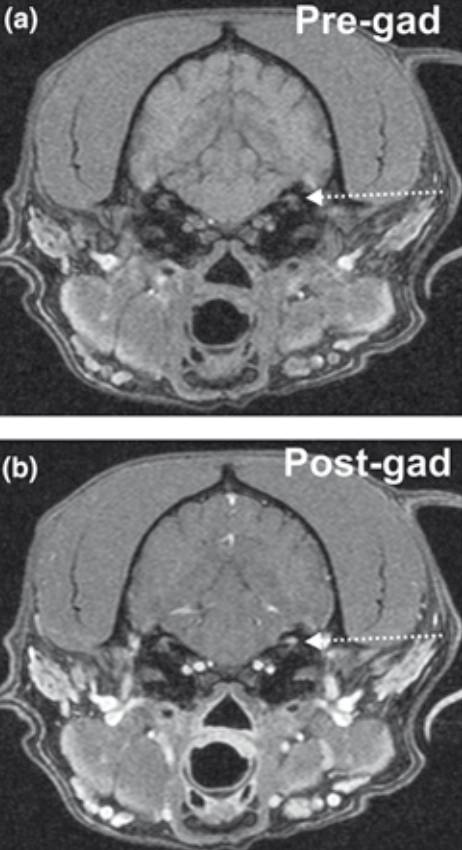

Is post-contrast T1w imaging or subtraction imaging better for detection of the meninges? Where (anatomically) was the enhancement predominately located?

Subtraction imaging allows clear visualization of the meninges

Appears as

Located in dura

What factor affects visualization of meningeal enhancement in post-gadolinium images?

Fat saturation was most useful (allowed definite diagnosis/characterization of meningeal enhancement in 50%)

Delay of image acquisition did not improve characterization of meningeal enhancement

No imaging features significantly allowed differentiation between neoplasia and inflammatory disease, but: